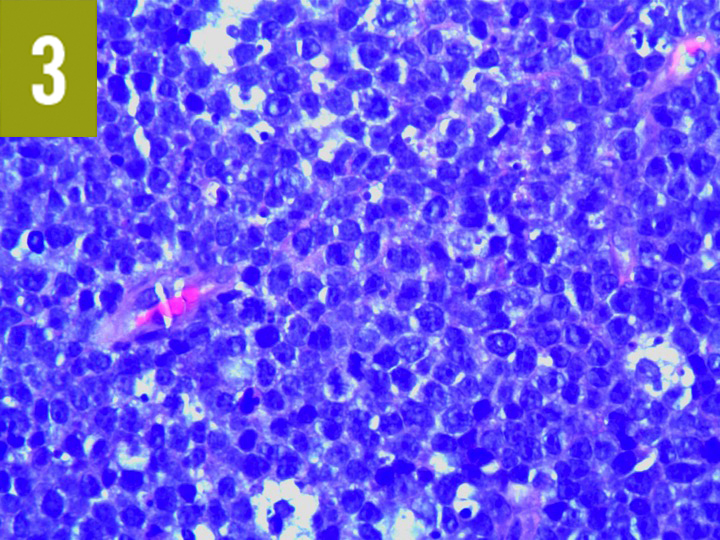

Pathologically BL is classically characterized by translocations of chromosomes 8 and 14 resulting in upregulation of the c-myc protein. There is a typical histopatho- logical appearance of densely clustered monomorphic small noncleaved cells in a classic starry sky pattern. Burkitt lymphoma BL is a highly aggressive B-cell non-Hodgkin lymphoma categorized into endemic sporadic and immunodeficiency-associated subtypes.

An aggressive tumour involving mostly abdomen jaw head neck and peripheral lymph node sites it. Histologically Burkitt lymphoma BL is characterized by a monoclonal proliferation of medium-sized noncleaved B-cells that are uniform in appearance and that produce a diffuse pattern of tissue. Which of the following factors are associated with Burkitts lymphoma formation.